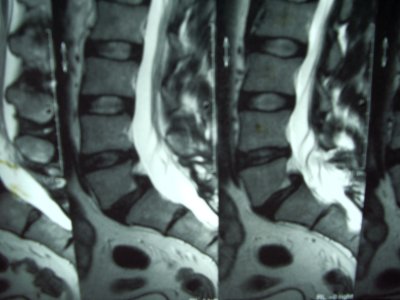

Espondilolistesis